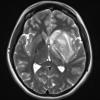

Mucormycosis - Zygomycosis